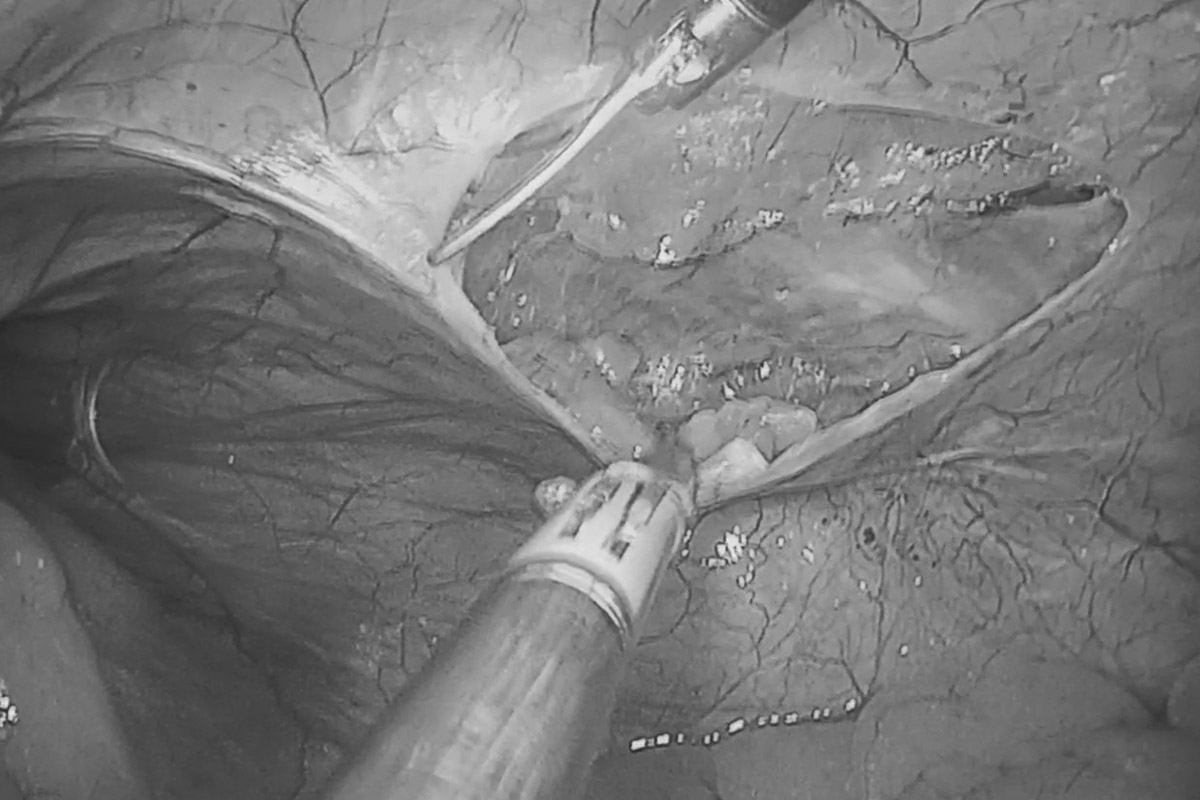

Лапароскопия — малоинвазивный метод иссечения паховой грыжи. Через небольшие проколы вводятся инструменты и лапароскоп, который позволяет контролировать ход операции на экране. Грыжевой мешок вправляется, и устанавливается протезная сетка, укрепляющая брюшную стенку. В ADONIS применяются сетки американского и французского производства, которые не требуют фиксации, что снижает болевой синдром и риск рецидивов. Восстановление проходит быстро, и пациент проводит в стационаре всего один день. Этот метод подходит для небольших грыж и требует общего наркоза.

- Лапароскопическая операция: Через небольшие проколы вводятся инструменты и лапароскоп. Грыжевой мешок вправляется, устанавливается сетка для укрепления брюшной стенки. Минимальный период реабилитации — пациент выписывается на следующий день.